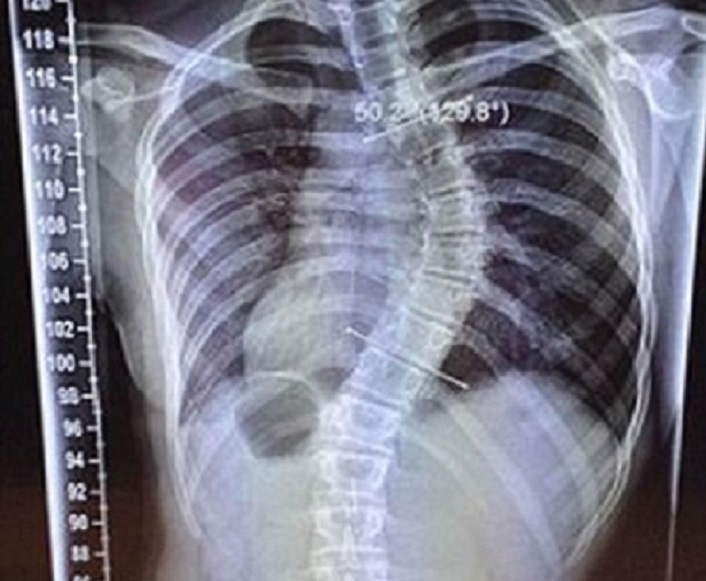

Một nữ vận động viên ở Anh suýt phải từ bỏ sự nghiệp thể thao khi xương sống của cô cong như quả chuối vì chiều cao tăng 15 cm trong vỏn vẹn hai tháng.